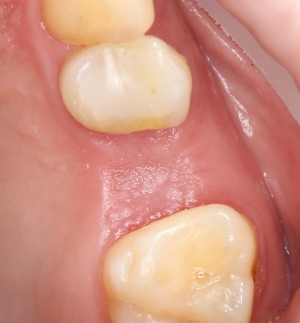

А вот так область операции выглядит через полтора месяца. Как видите, мы сохранили как объем альвеолярного гребня, так и кератинизированной десны:

И теперь наша клиническая ситуация — просто мечта для имплантолога!

Ничего не стоит поставить имплантат в такие объемы кости и при таком качестве слизистой оболочки:

Обратите внимание: даже там, где отсутствовала вестибулярная стенка лунки, восстановилась костная ткань:

Теперь мы просто ставим имплантат. Без синуслифтинга. И без проблем со стабилизацией:

А качество и объем слизистой оболочки настолько хороши, что можно сразу поставить формирователь десны:

и через 3 месяца приступить к протезированию:

Итого: 4,5 месяца, удаление-аугментация лунки плюс имплантация-формирование десны. Всего две операции. И никаких проблем.